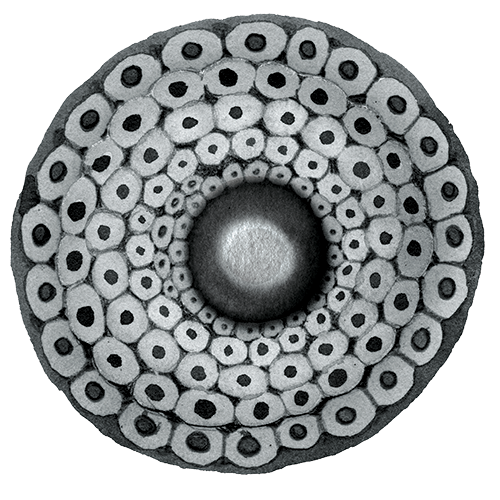

How an egg retrieval works

It’s bustling but quiet as two doctors and three nurses play parts performed so often it’s now second nature. On the wall, a screen displays the transvaginal ultrasound of Karen’s right ovary. After a two-week regimen of hormones, it’s swollen four times in size. Beneath the projection of stars, the grainy image could be a moonscape pocked with a dozen dark craters.

Each crater is a follicle. WeFIV’s chief physician guides the needle through the recesses of Karen’s body, piercing the vaginal wall to reach the ovary. One by one, the follicles are drained of their liquid. Karen snores. The craters disappear from the screen. Karen squirms, and a nurse adjusts her back into position. The fluid is deposited into vials.

Around that time, researchers began experimenting with freezing eggs. Success rates were low. The human egg is 90% water, and when it freezes, ice crystals can damage the delicate spindle of chromosomes inside. Even as IVF became mainstream, only a few births using frozen eggs occurred over the next two decades.

By the early 2000s a new technology, known as vitrification, allowed eggs to be frozen so quickly that the fluid has no time to form crystals and instead turns into a glasslike solid. In 2012 two of the world’s largest organizations representing fertility practitioners backed the technique. Vitrification boomed. In the US alone, the number of fertility procedures using frozen donor eggs or embryos tripled from 2012 to 2021, to 26,700, according to the Centers for Disease Control and Prevention.